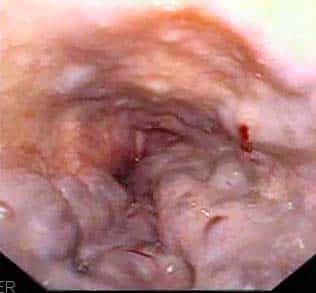

The oesophagus is a fibromuscular tube, approximately 25cm in length, that transports food from the pharynx to the stomach. It originates at the inferior border of the cricoid cartilage (C6) and extends to the cardiac orifice of the stomach (T11). In this article we shall examine the anatomy of the oesophagus – its structure, vascular supply and clinical correlations. By TeachMeSeries Ltd (2025) Fig 1.0The oesophagus Pro Feature - 3D Model You've Discovered a Pro Feature Access our 3D Model Library Explore, cut, dissect, annotate and manipulate our 3D models to visualise anatomy in a dynamic, interactive way. Learn More Anatomical Course The oesophagus begins in the neck, at the level of C6. Here, it is continuous superiorly with the laryngeal part of the pharynx (the laryngopharynx). It descends downward into the superior mediastinum of the thorax, positioned between the trachea and the vertebral bodies of T1 to T4. It then enters the abdomen via the oesophageal hiatus (an opening in the right crus of the diaphragm) at T10. The abdominal portion of the oesophagus is approximately 1.25cm long – it terminates by joining the cardiac orifice of the stomach at level of T11. Pro Feature - Dissection Images Dissection of the thorax, demonstrating the passage of the oesophagus, inferior vena cava and descending aorta through the diaphragm. Note how the right crus of the diaphragm has a 'pinch-cock' effect on the oesophagus to form the lower oesophageal sphincter Dissection of the thorax, demonstrating the passage of the oesophagus, inferior vena cava and descending aorta through the diaphragm. Note how the right crus of the diaphragm has a 'pinch-cock' effect on the oesophagus to form the lower oesophageal sphincter You've Discovered a Pro Feature Access our Dissection Image Library Enhance your understanding with high-resolution dissection images showcasing real-life anatomy. Learn More Anatomical Structure The oesophagus shares a similar structure with many of the organs in the alimentary tract: Adventitia – outer layer of connective tissue. Note: The very distal and intraperitoneal portion of the oesophagus has an outer covering of serosa, instead of adventitia. Muscle layer – external layer of longitudinal muscle and inner layer of circular muscle. The external layer is composed of different muscle types in each third: Superior third – voluntary striated muscle Middle third – voluntary striated and smooth muscle Inferior third – smooth muscle Submucosa Mucosa – non-keratinised stratified squamous epithelium (contiguous with columnar epithelium of the stomach). Food is transported through the oesophagus by peristalsis – rhythmic contractions of the muscles which propagate down the oesophagus. Hardening of these muscular layers can interfere with peristalsis and cause difficulty in swallowing (dysphagia). Adapted from work by Cancer Research UK [CC BY-SA 4.0] Fig 2The layers of the oesophagus. The muscle layer is further divided into an outer longitudinal layer and inner circular layer. Oesophageal Sphincters There are two sphincters present in the oesophagus, known as the upper and lower oesophageal sphincters. They act to prevent the entry of air and the reflux of gastric contents respectively. Upper Oesophageal Sphincter The upper sphincter is an anatomical, striated muscle sphincter at the junction between the pharynx and oesophagus. It is produced by the cricopharyngeus muscle. Normally, it is constricted to prevent the entrance of air into the oesophagus. Lower Oesophageal Sphincter The lower oesophageal sphincter is located at the gastro-oesophageal junction (between the stomach and oesophagus). The gastro-oesophageal junction is situated to the left of the T11 vertebra, and is marked by the change from oesophageal to gastric mucosa. The sphincter is classified as a physiological (or functional) sphincter, as it does not have any specific sphincteric muscle. Instead, the sphincter is maintained by four factors: Oesophagus enters the stomach at an acute angle. Walls of the intra-abdominal section of the oesophagus are compressed when there is a positive intra-abdominal pressure. Prominent mucosal folds at the gastro-oesophageal junction aid in occluding the lumen. Right crus of the diaphragm has a “pinch-cock” effect. During oesophageal peristalsis, the sphincter is relaxed to allow food to enter the stomach. Otherwise at rest, the function of this sphincter is to prevent the reflux of acidic gastric contents into the oesophagus. Anatomical Relations The anatomical relations of the oesophagus give rise to four physiological constrictions in its lumen – it is these areas where food/foreign objects are most likely to become impacted. They can be remembered using the acronym ‘ABCD‘: Arch of aorta Bronchus (left main stem) Cricoid cartilage Diaphragmatic hiatus The table below lists the anatomical relations of the oesophagus: Anterior Posterior Right Left Cervical and thoracic Trachea Left recurrent laryngeal nerve Pericardium Thoracic vertebral bodies Thoracic duct Azygous veins Descending aorta Pleura Terminal part of azygous vein Subclavian artery Aortic arch Thoracic duct Pleura Abdominal Left vagus nerve Posterior surface of the heart Right vagus nerve Left crus of the diaphragm Vasculature In respect to its arterial and venous supply, the oesophagus can be divided into its thoracic and abdominal components. Thoracic The thoracic part of the oesophagus receives its arterial supply from the branches of the thoracic aorta and the inferior thyroid artery (a branch of the thyrocervical trunk). Venous drainage into the systemic circulation occurs via branches of the azygous veins and the inferior thyroid vein. Abdominal The abdominal oesophagus is supplied by the left gastric artery (a branch of the coeliac trunk) and left inferior phrenic artery. This part of the oesophagus has a mixed venous drainage via two routes: To the portal circulation via left gastric vein To the systemic circulation via the azygous vein. These two routes form a porto-systemic anastomosis, a connection between the portal and systemic venous systems. By TeachMeSeries Ltd (2025) Fig 3Posterior view of the oesophagus. Some of the thoracic vasculature is noted. Innervation The oesophagus is innervated by the oesophageal plexus, which is formed by a combination of the parasympathetic vagal trunks and sympathetic fibres from the cervical and thoracic sympathetic trunks. Two different types of nerve fibre run in the vagal trunks. The upper oesophageal sphincter and upper striated muscle is supplied by fibres originating from the nucleus ambiguus. Fibres supplying the lower oesophageal sphincter and smooth muscle of the lower oesophagus arise from the dorsal motor nucleus. Lymphatics The lymphatic drainage of the oesophagus is divided into thirds: Superior third – deep cervical lymph nodes. Middle third – superior and posterior mediastinal nodes. Lower third – left gastric and celiac nodes. Clinical Relevance Disorders of the Oesophagus Barrett’s Oesophagus Barrett’s oesophagus refers to the metaplasia (reversible change from one differentiated cell type to another) of lower oesophageal squamous epithelium to gastric columnar epithelium. It is usually caused by chronic acid exposure as a result of a malfunctioning lower oesophageal sphincter. The acid irritates the oesophageal epithelium, leading to a metaplastic change. The most common symptom is a long-term burning sensation of indigestion. It can be detected via endoscopy of the oesophagus. Patients who are found to have it will be monitored for any cancerous changes. Oesophageal Carcinoma Around 2% of malignancies in the UK are oesophageal carcinomas. The clinical features of this carcinoma are: Dysphagia – difficulty swallowing. It becomes progressively worse over time as the tumour increases in size, restricting the passage of food. Weight loss There are two major types of oesophageal carcinomas: squamous cell carcinoma and adenocarcinoma. Squamous cell carcinoma – the most common subtype of oesophagus cancer. It can occur at any level of the oesophagus. Adenocarcinoma – only occurs in the inferior third of the oesophagus and is associated with Barrett’s oesophagus. It usually originates in the metaplastic epithelium of Barrett’s oesophagus. Oesophageal Varices The abdominal oesophagus drains into both the systemic and portal circulation, forming an anastomosis between the two. Oesophageal varices are abnormally dilated sub-mucosal veins (in the wall of the oesophagus) that lie within this anastomosis. They are usually produced when the pressure in the portal system increases beyond normal, a state known as portal hypertension. Portal hypertension most commonly occurs secondary to chronic liver disease, such as cirrhosis or an obstruction in the portal vein. The varices are predisposed to bleeding, with most patients presenting with haematemesis (vomiting of blood). Alcoholics are at a high risk of developing oesophageal varices. By TeachMeSeries Ltd (2025) Fig 4Endoscopic view of oesophageal varices Do you think you’re ready? Take the quiz below Pro Feature - Quiz The Oesophagus Question 1 of 3 Submitting... Skip Next Rate question: You scored 0% Skipped: 0/3 1800 More Questions Available Upgrade to TeachMeAnatomy Pro Challenge yourself with over 1800 multiple-choice questions to reinforce learning Learn More Rate This Article